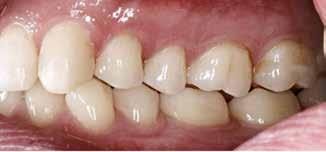

Fig. 3. Kofferdam blev anlagt sektionsvis for at opnå god fugtighedskontrol. Fig. 3. Rubber dam was applied section wise to achieve appropriate moisture control.

okklusal-vertikale dimension. De afficerede dentinoverflader blev ridset i overfladen med en grov diamant, men derudover blev der ikke foretaget nogen form for kavitetspræparation, da intentionen var at gennemføre en minimalt invasiv behandlingstilgang. Kofferdam blev anlagt i hvert arbejdsfelt (Fig. 3) og adhæsivet påført med en æts-og-skyl-strategi (ætsning af emalje og dentin, primer, adhæsiv). Derefter blev tænderne bygget op med en mikrohybrid komposit for at genskabe tandens naturlige form (Fig. 4). I underkæbefronten blev der kun lagt et tyndt lag med komposit pga. pladsmangel. Efter omhyggelig pudsning og polering havde patienten okklusion på samtlige tænder og var tilfreds med både funktion og æstetik.

Restaurering af et slidt tandsæt ved hjælp af adhæsiv teknik og direkte komposit er tidkrævende og teknisk udfordrende. Det kræver gode procedurer at opretholde en nødvendig og god intraoral fugtighedskontrol over længere tid. Anvendelse af kofferdam er i disse tilfælde et godt hjælpemiddel, som giver god isolation af arbejdsfeltet. Ulemperne er, at operatøren mister overblikket over hele tandsættet og ikke er i stand til at kontrollere okklusion og relation til andre tænder undervejs i behandlingen. Løsningen kan da være at montere kofferdamdugen og restaurere tænder sektionsvis med kontrol af relationer indimellem (Fig. 3).